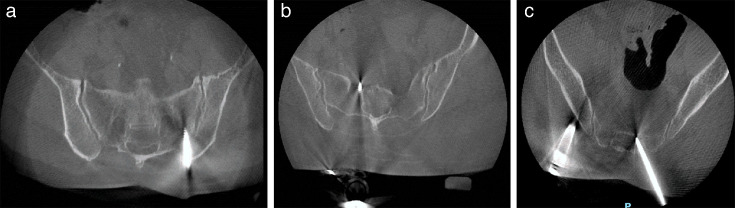

Methods: This is a single-centre, institutional board approved, multisurgeon retrospective analysis of 69 included DRB placements from 51 robot-assisted lumbar posterior instrumentation procedures between May 2022 and April 2024. Pin entry point and trajectory were mapped out; the intraoperative O-arm CT scans and skin-to-PSIS depth were also measured, and patient demographics (age, sex, BMI), surgical outcomes, and postoperative complications were recorded.

Results: Of the 69 PSIS pin placements, 47 (68.1%) had the correct entry point on the PSIS, and 35 (50.7%) of them were placed correctly within the ilium without breaching a second cortex. Skin-to-PSIS depth was significantly higher in patients with misplaced DRB placement, while age, sex, and BMI were similar. Of those with misplaced DRB (n = 34), one had delayed pin site wound healing.